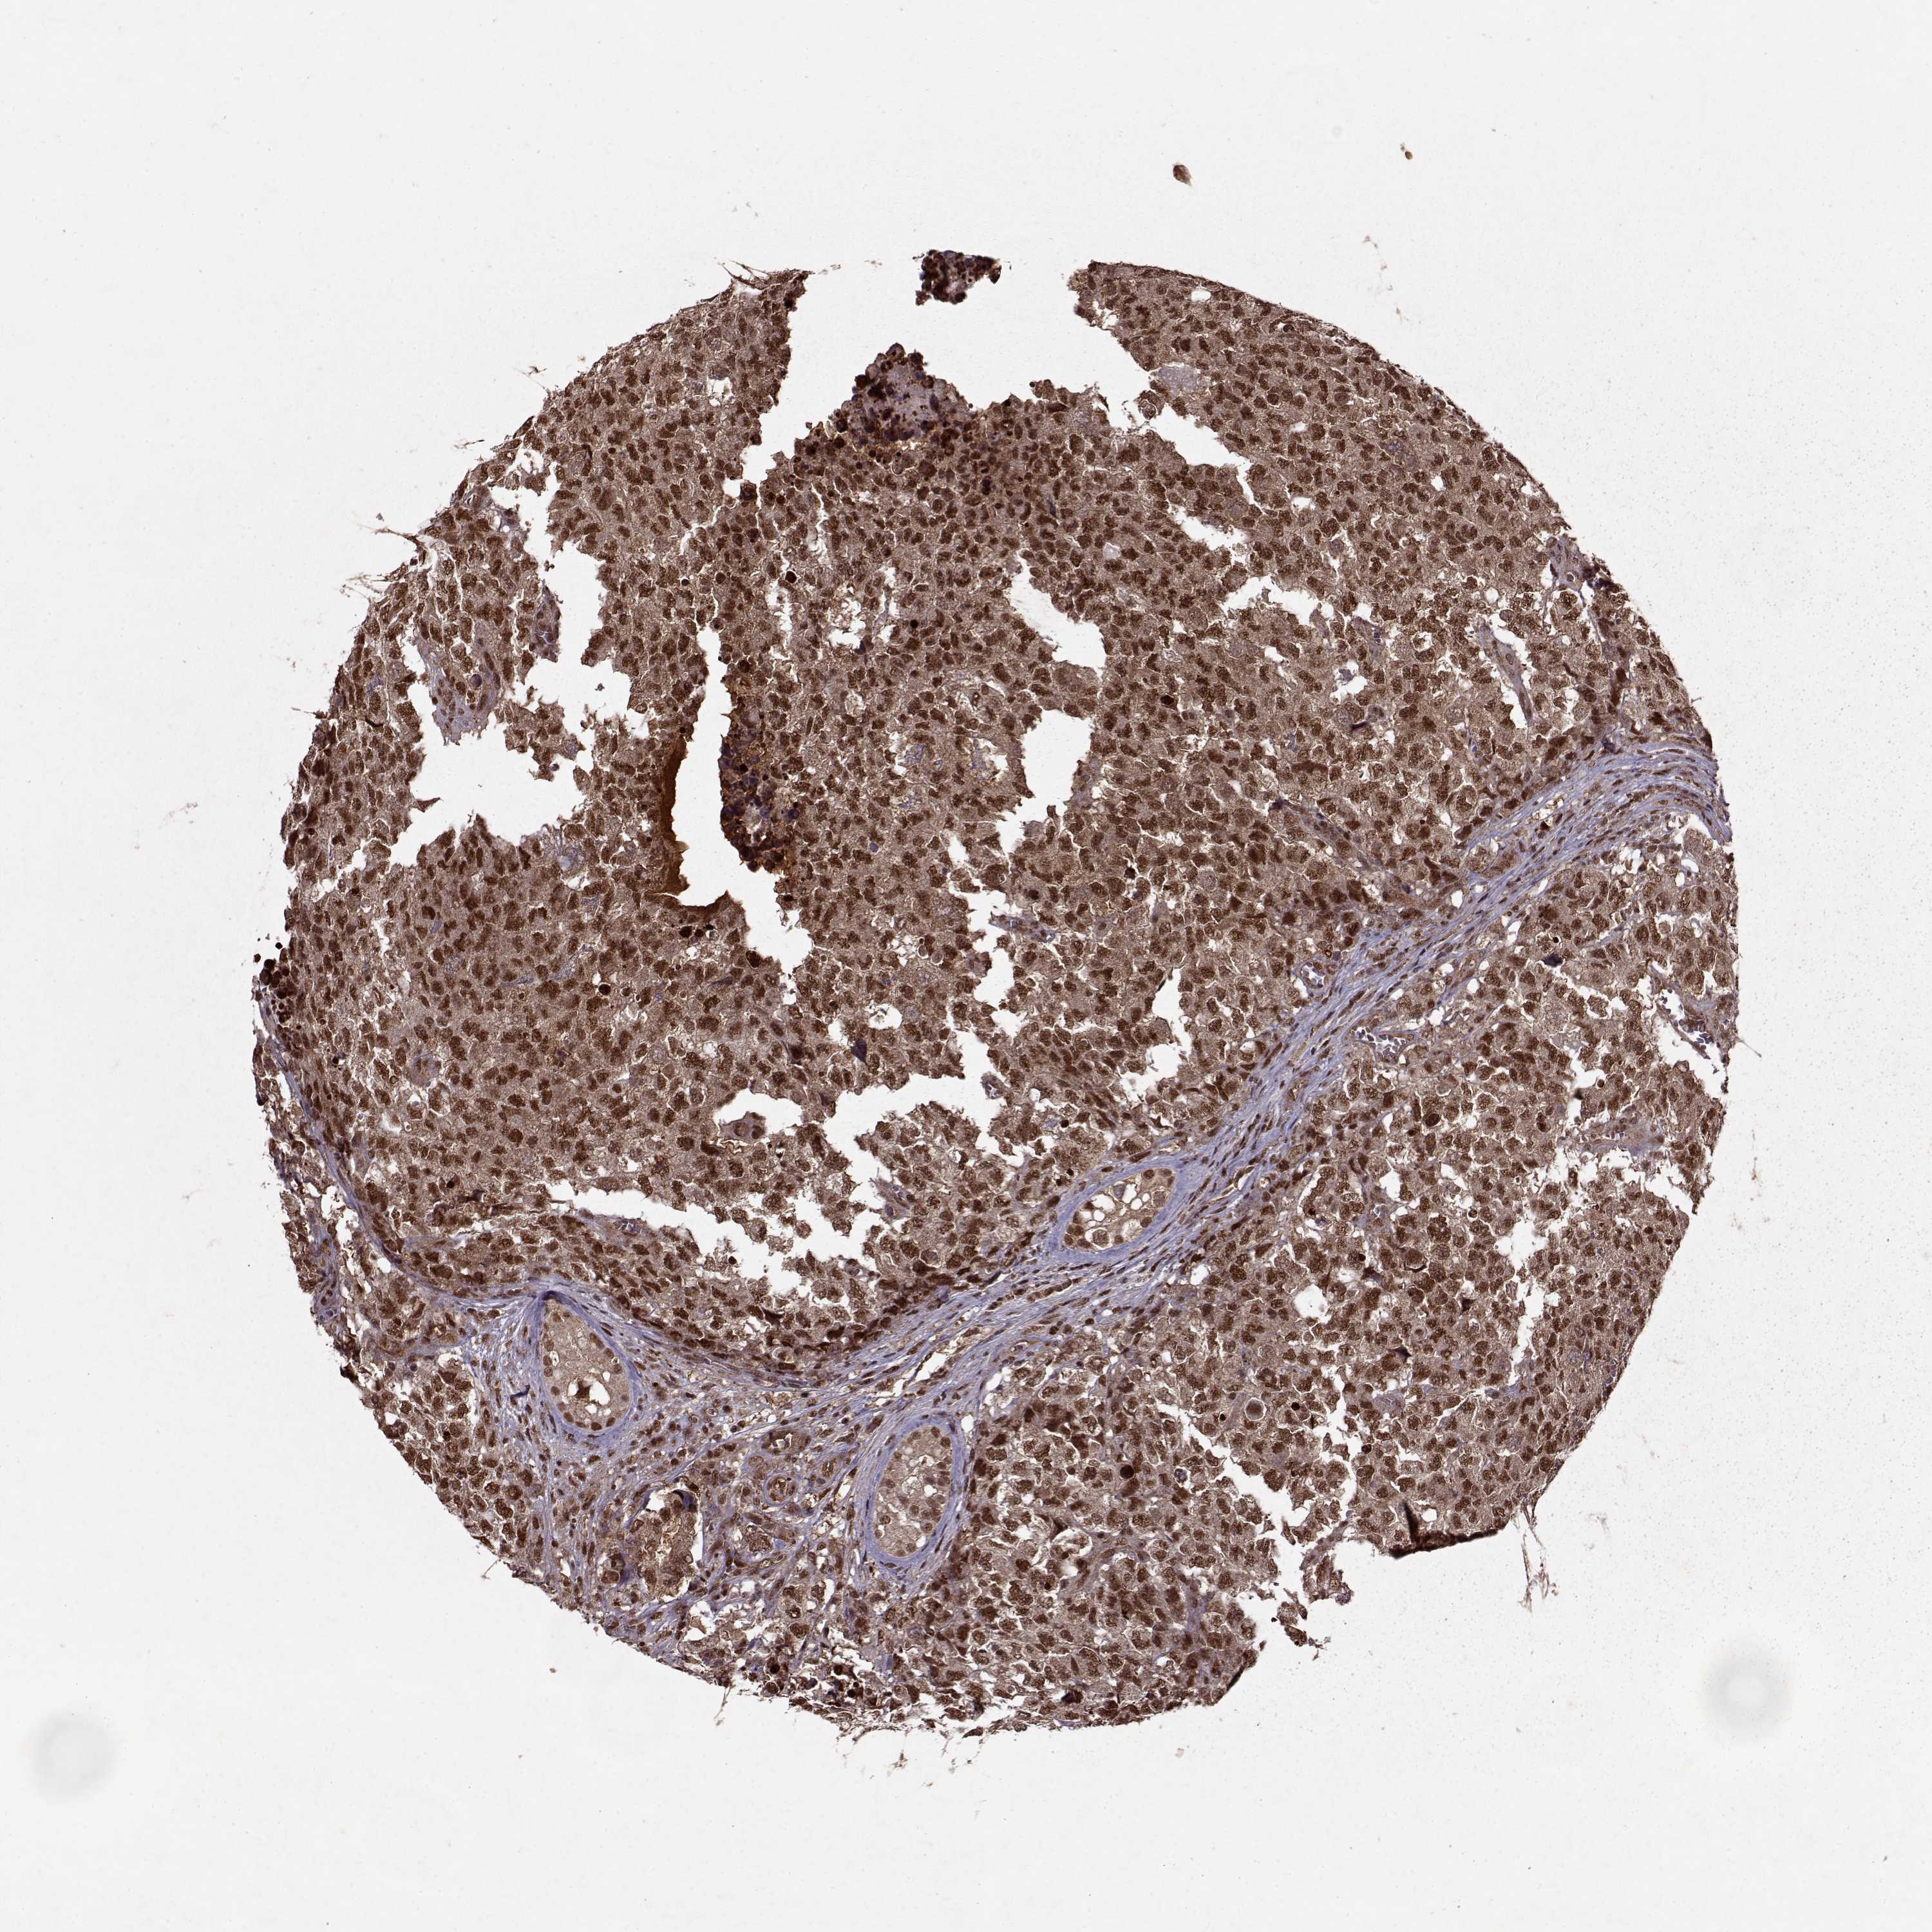

TESTIS CANCER - Protein expressioni

A mouse-over function shows sample information and annotation data. Click on an image to view it in a full screen mode. Samples can be filtered based on level of antibody staining by selecting one or several of the following categories: high, medium, low and not detected. The assay and annotation is described here.

Note that samples used for immunohistochemistry by the Human Protein Atlas do not correspond to samples in the TCGA dataset.

Antibody stainingi

Antibody staining in the annotated cell types in the current human tissue is reported as not detected, low, medium, or high, based on conventional immunohistochemistry profiling in selected tissues. This score is based on the combination of the staining intensity and fraction of stained cells.

Each image is clickable and will lead to virtual microscopy that enables deeper exploration of all samples and also displays staining intensity scores, fraction scores and subcellular localization as well as patient and tissue information for each sample.

Antibody CAB046008

Carcinoma, Embryonal, NOS

Seminoma, NOS

Teratoma, malignant, NOS